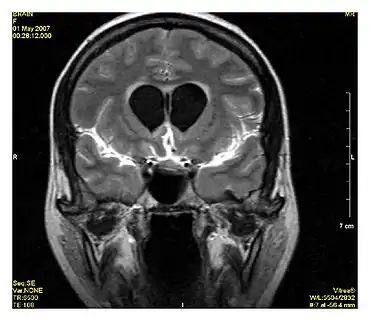

MR angiogram in congenital heart disease

Cardiac MRI is complementary to other imaging techniques, such as echocardiography, cardiac CT, and nuclear medicine. It can be used to assess the structure and the function of the heart.[30] Its applications include assessment of myocardial ischemia and viability, cardiomyopathies, myocarditis, iron overload, vascular diseases, and congenital heart disease.[31]